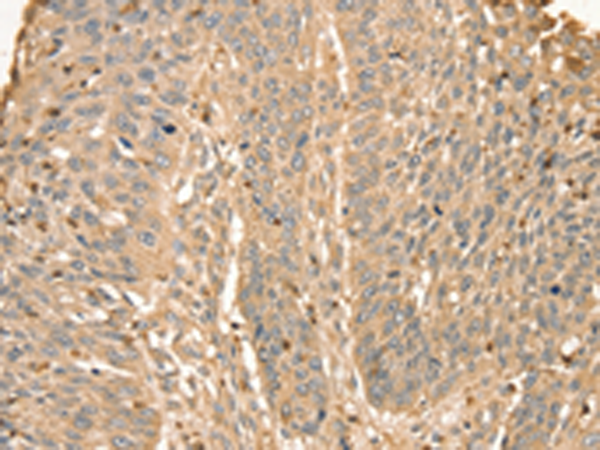

分类: 科研抗体货号: P08731别名: p6; CAGC; CGRP; MRP6; CAAF1; MRP-6; ENRAGE应用: IHC反应种属: Human